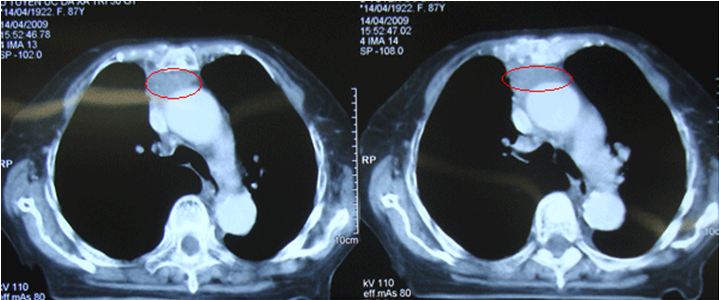

Kết quả chụp CT scanner lồng ngực:

Ngày 06/03/2009Ngày 14/04/2009Ngày 27/04/2009

Khối tỷ trọng tổ chức tại vị trí tuyến ức, ngấm thuốc sau tiêm, không thấy vôi hóa, bờ khối không đều, kích thước 38x30 mm

Dịch màng ngoài timSố lượng nhiềuTràn dịch khoang màng ngoài timDịch màng ngoài tim lượng ít, giảm so với phim trước

Dịch màng phổiDịch màng phổi (P) lượng ítKhoang màng phổi 2 bên không có dịch, khíKhoang màng phổi 2 bên không có dịch, khí.

Hình ảnh sau điều trị